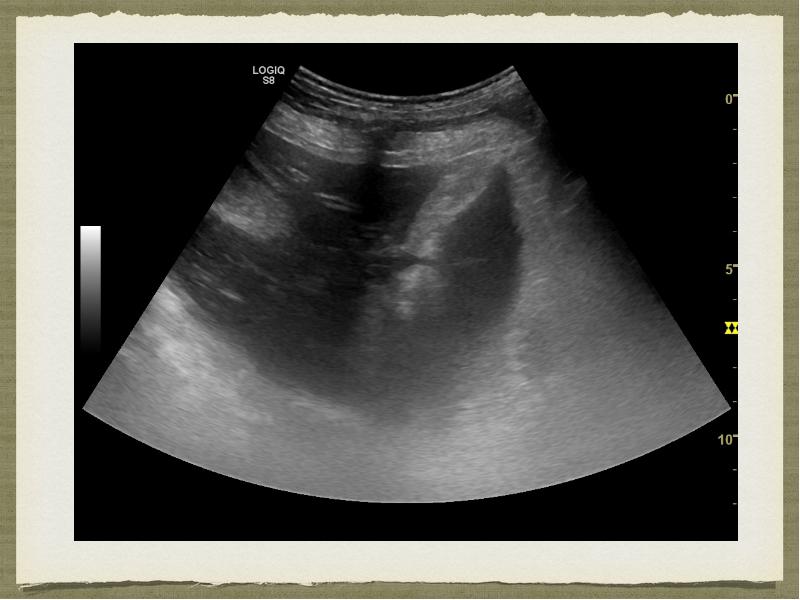

- 8. Ультразвуковое исследование Описание: …в области ворот печени справа доля печени (сосцевидная?